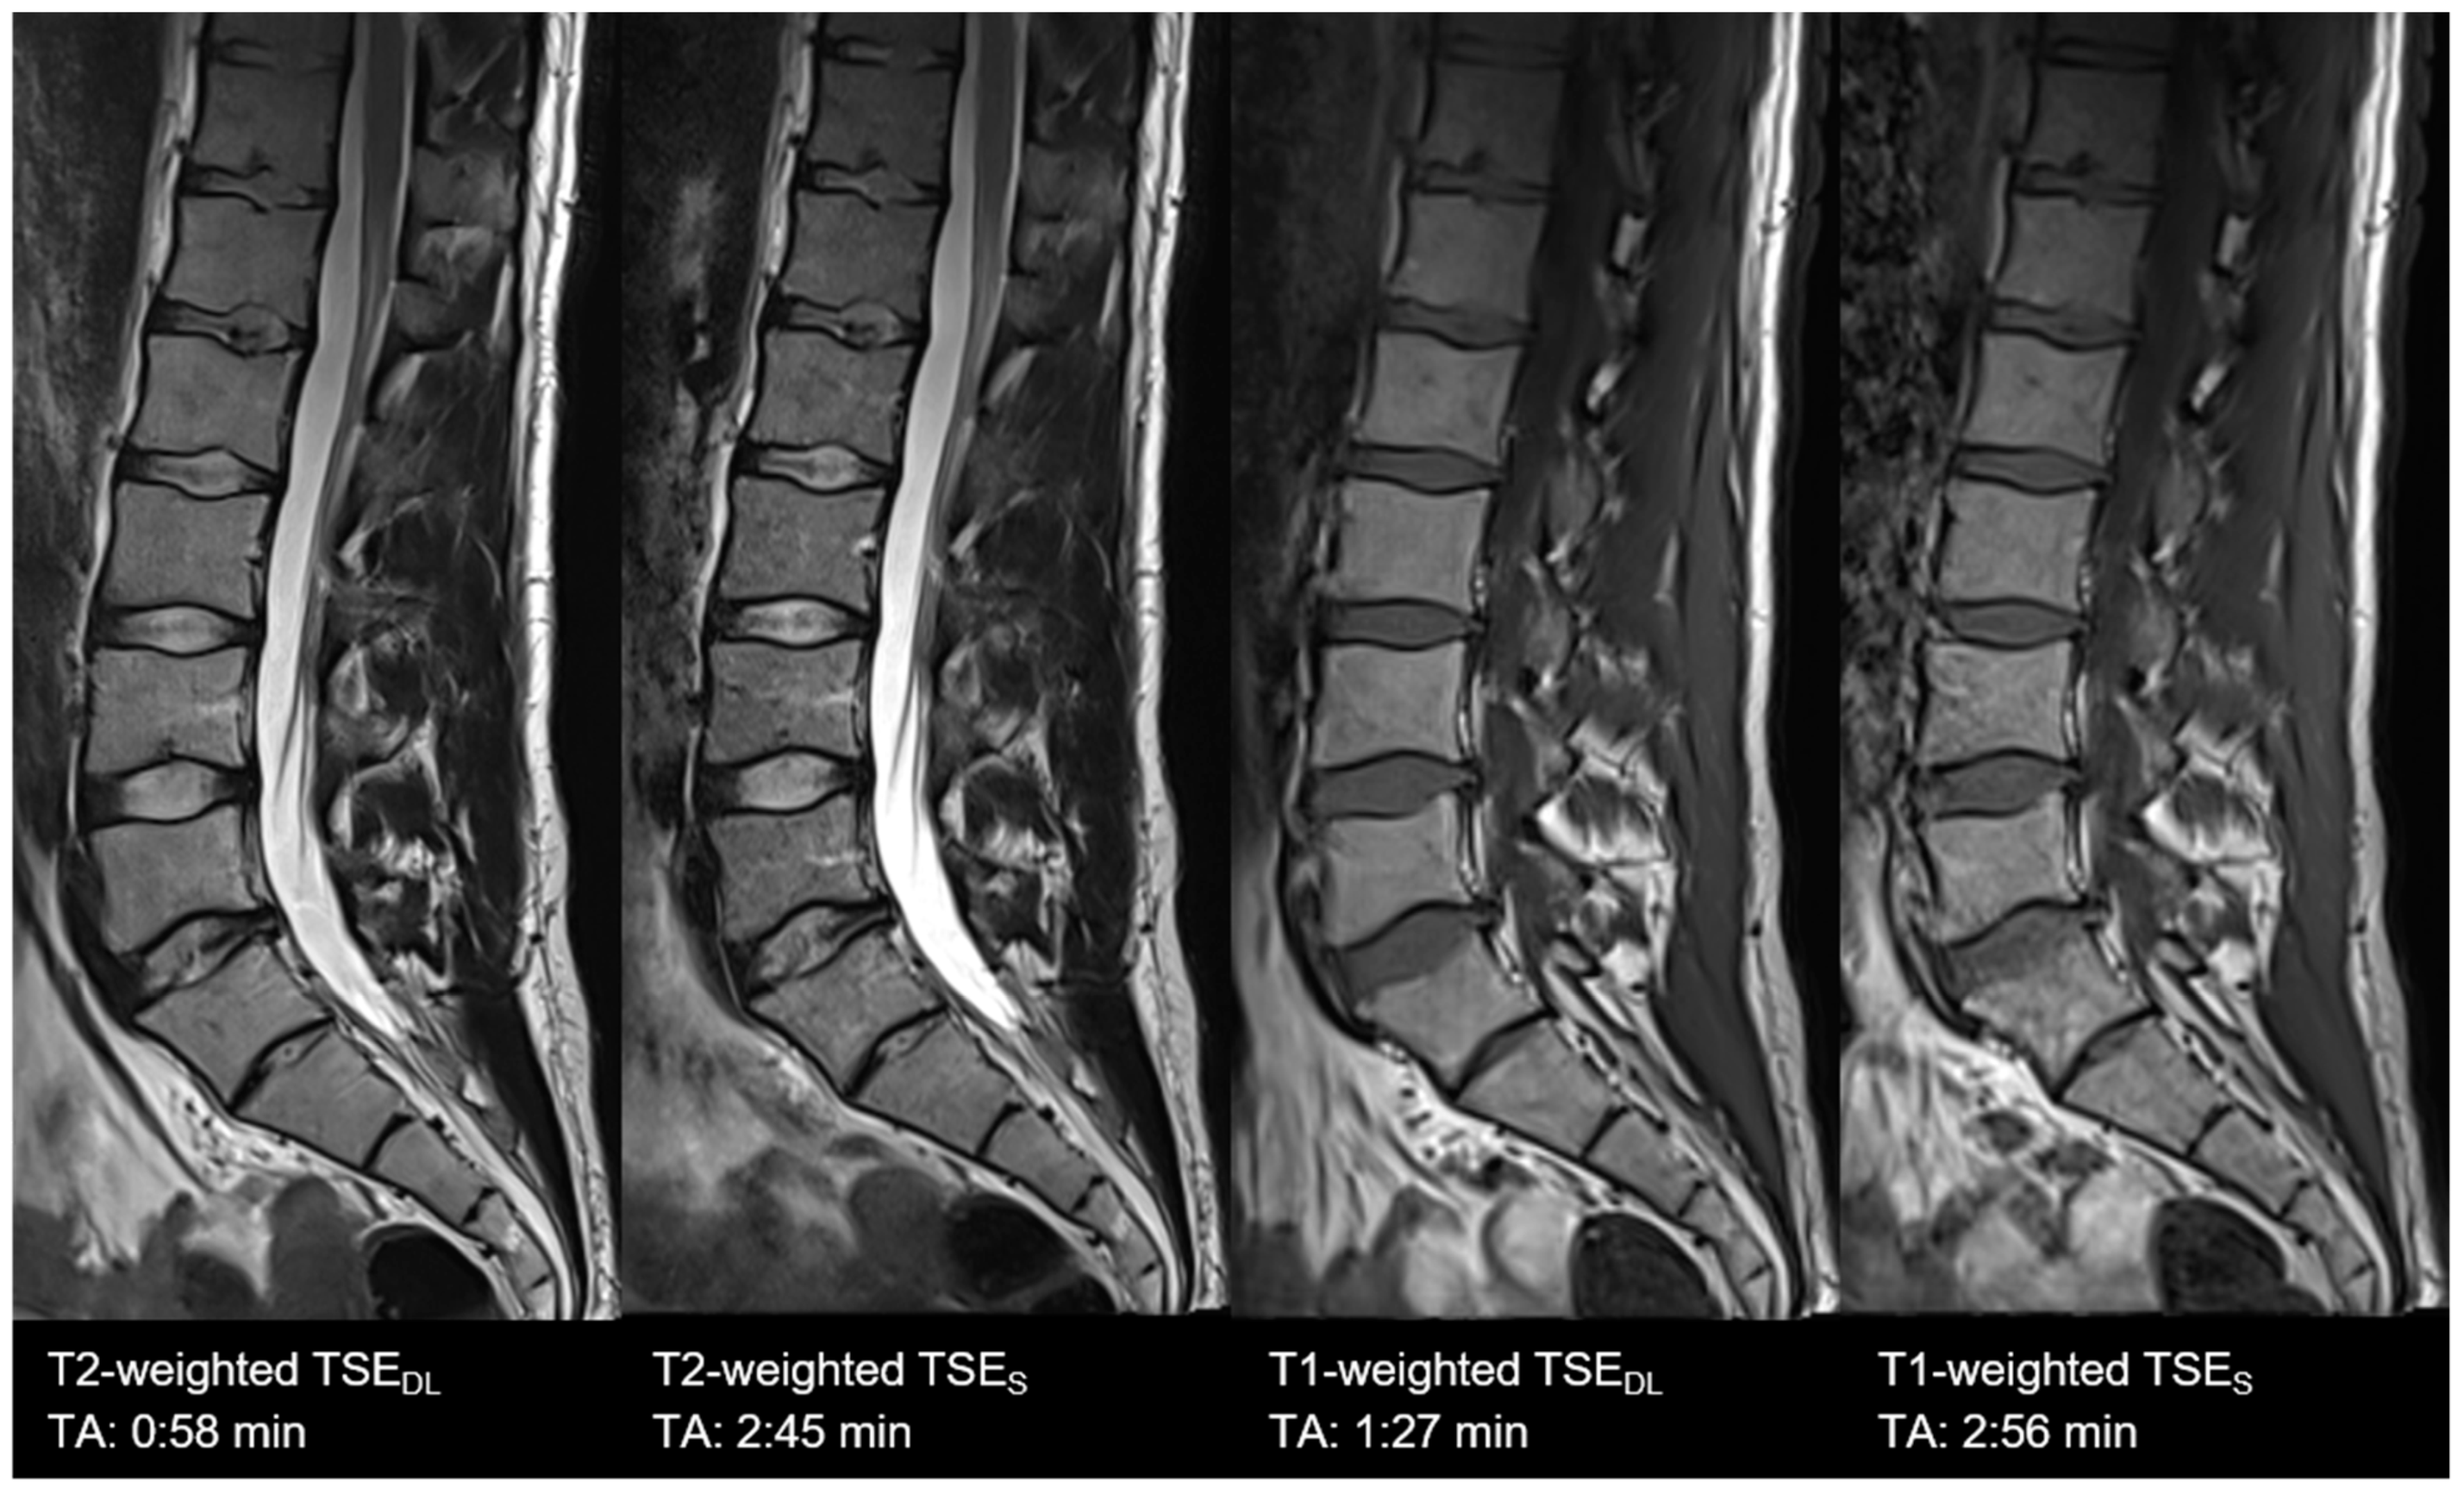

| Lumbar spine | TSES | T1 TSE | sagittal | 2:56 | 300 | 0.9 × 0.9 × 3.0 | 1 | 2 | 0 | 562 | 10 | 150 | 180 | 10.4 |

| T2 TSE FS | sagittal | 2:45 | 300 | 0.7 × 0.7 × 3.0 | 2 | 1 | 2 | 6040 | 102 | 150 | 189 | 11.3 | ||

| TSEDL | T1 TSE | sagittal | 1:27 | 300 | 0.9 × 0.9 × 3.0 | 1 | 2 | 3 | 462 | 10 | 150 | 180 | 10.4 | |

| T2 TSE FS | sagittal | 0:58 | 300 | 0.7 × 0.7 × 3.0 | 1 | 1 | 3 | 4470 | 105 | 150 | 189 | 10.5 | ||